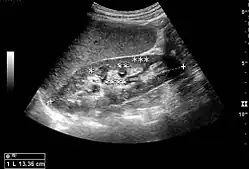

Complex cysts can have membranes dividing the fluid-filled center with internal echoes, calcifications or irregular thickened walls. The complex cyst can be further evaluated with Doppler US, and for Bosniak classification and follow-up of complex cysts, either contrast-enhanced ultrasound (CEUS) or contrast CT is used (Figure 6). The Bosniak classification is divided into four groups going from I, corresponding to a simple cyst, to IV, corresponding to a cyst with solid parts and an 85–100% risk of malignancy.[1] In polycystic kidney disease, multiple cysts of varying size in close contact with each other are seen filling virtually the entire renal region. In advanced stages of this disease, the kidneys are enlarged with a lack of corticomedullary differentiation (Figure 7).[1]

Figure 7. Advanced polycystic kidney disease with multiple cysts.[1]